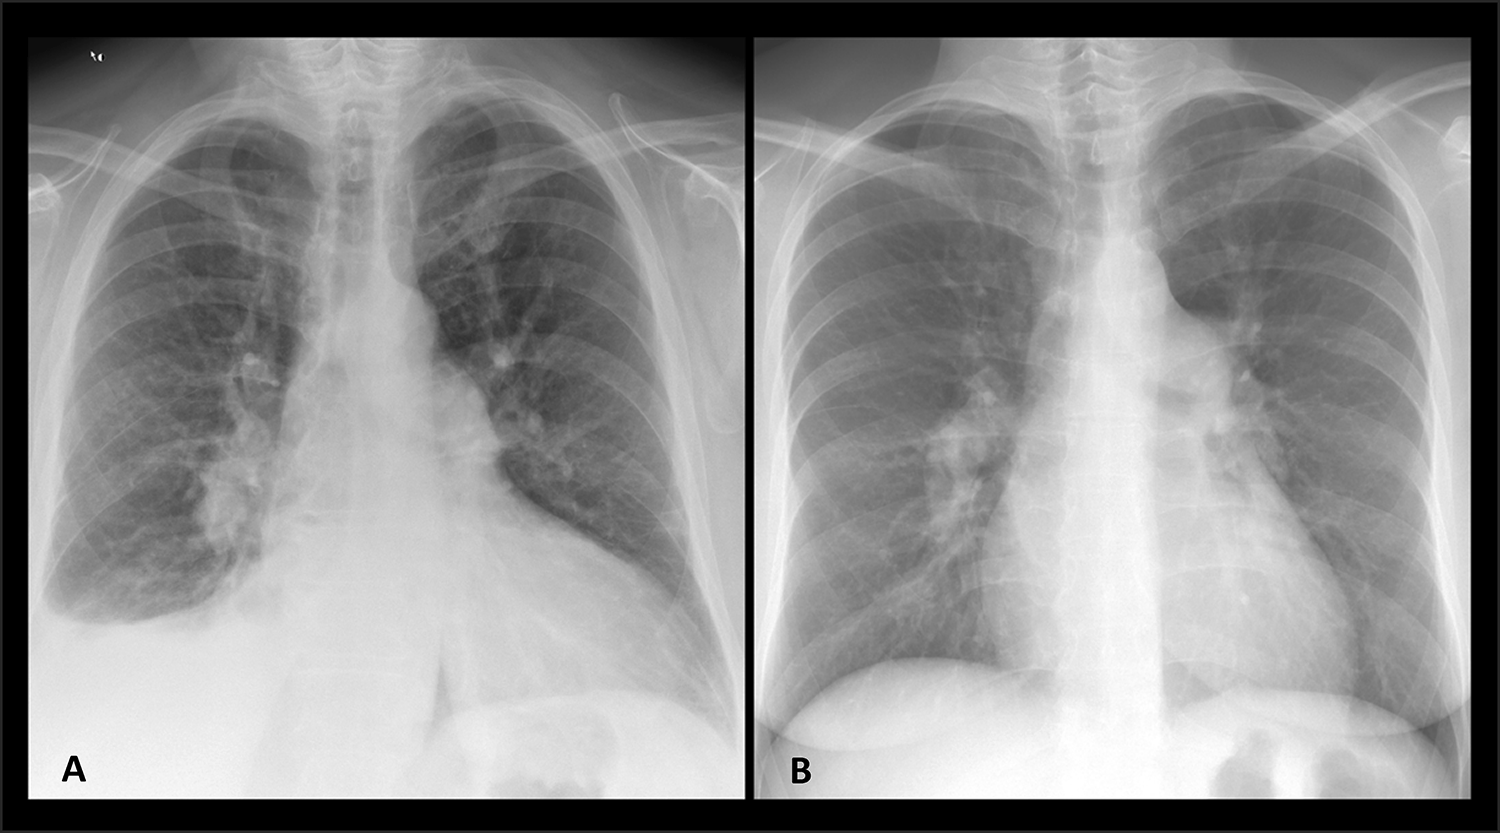

Fig. 6

Frontal Chest X-Ray images from 2 Study Population subjects represent the PVPs of both forms of cardiopulmonary-derived Pre-Capillary PH, including: CpcPH: Main and central pulmonary artery dilatation superimposed on PVH (Stage 2-Late in this case) (A). Group 1 PH: Main and central pulmonary artery dilatation without PVH, lung disease, etc. (B). CpcPH : Combined pre-/post-capillary Pulmonary hypertension PH: Pulmonary Hypertension, PVH: Pulmonary Venous Hypertension, PVP: Pulmonary Vasculature Pattern.